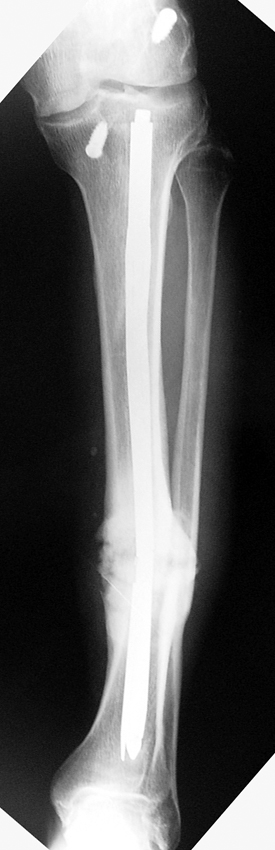

Vaka 1